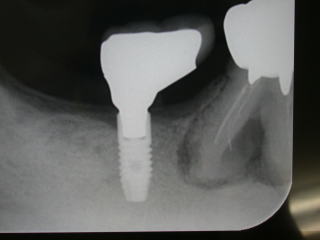

症例10、60才代男性、(新潟県長岡市要町、要町歯科、インプラント)

右下7番の欠損部分にインプラントを植立しました。

インプラント稙立は2018年4月6日。

上部構造物(白い歯)の装着は2019年9月28日です。